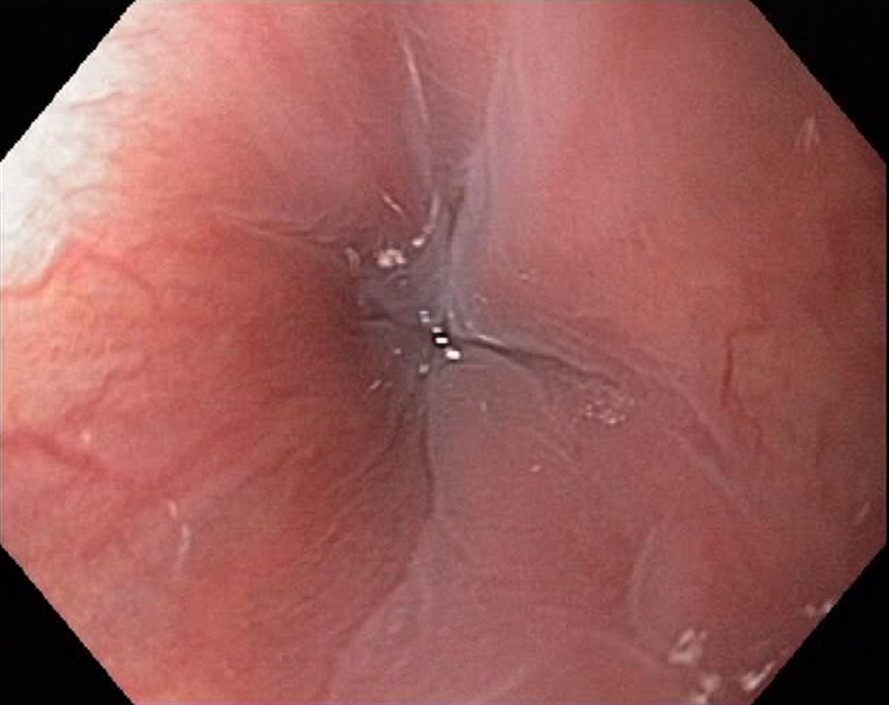

Achalasia cardiae is a motility disorder of the oesophagus, where there is a nerve degeneration in the Auerbach´s plexus, causing inability of the lower oesophageal sphincter in the cardia region (C) to relax. In oesophageal x-ray examanations a dilatation of the oesophagus is seen, and the contrast stays in the oesophagus for a long time. Endoscopy shows a quite normal cardia, and in less severe cases the endoscopic diagnose is not easy. Dysphagia is the main symptom, causing weight loss in severe cases. Achalasia can be treated with medicines (nifedipine, nitrates), botulinumtoxin injections in the cardia, dilatation during endoscopy and surgically (Heller´s myotomy).